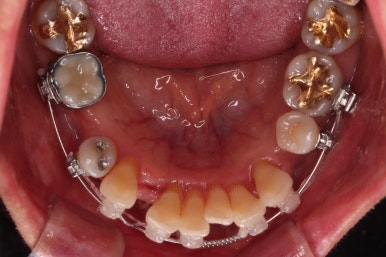

동래임플란트교정 마무리 되었습니다.

임플란트 머리도 잘 올라갔고, 치열도 가지런해졌으며 교합이나 중앙선도 적절히 마무리 되었습니다.

전후 비교를 해보겠습니다.

웃는 모습이 매우 우아해지셨어요.

미소가 굉장히 예뻐지셨습니다.

더군다나 예상한대로 발치교정으로 입을 많이 넣었음에도 팔자주름이나 피부처짐이 없이 잘 마무리 되었습니다.

이상 발치교정으로 입매를 개선하고 치열을 가지런하게 한 뒤 임플란트까지 잘 마무리를 한 동래임플란트교정 치료사례였습니다.